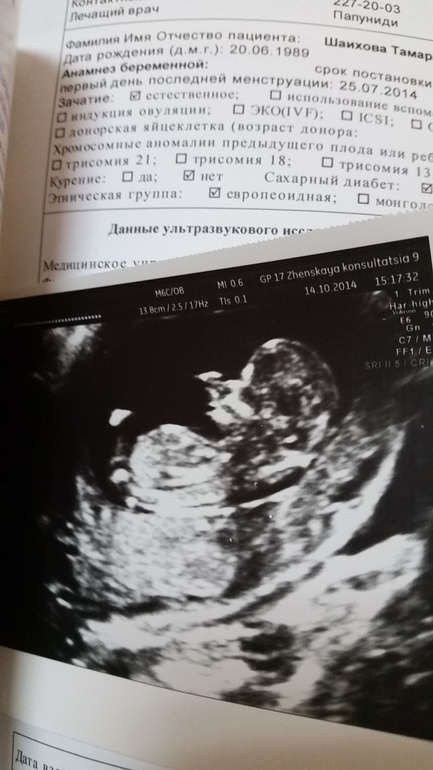

вторая БДолгожданное первое узи было только что. С полом пока не понятно , сверху мальчик а внутренним датчиком девочка. С никитосом сразу сказали мальчик . Так что будем надеяться на девочкую. Здоровенький малыш ,увидила как бъется сердечко , как он шевелится . Сначала ручками шевелил потом ко мне попой повернулся , мой сладенький.

14.10.2014